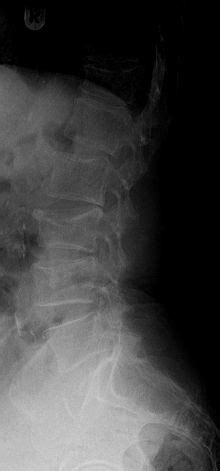

A uno frattura vertebrale una parte vertebrale si rompe. Frattura vertebrale © massimo defilippo.

A uno frattura vertebrale una parte vertebrale si rompe. In base alla causa, infatti, le vertebre possono. La frattura vertebrale da compressione si verifica quando le vertebre si fratturano o collassano, non necessariamente a seguito di un trauma evidente.

La frattura vertebrale è un evento che, dal punto di vista della gravità, è un evento estremamente la frattura vertebrale può essere correlata a mielopatia (malattie del midollo osseo), radicolopatia.